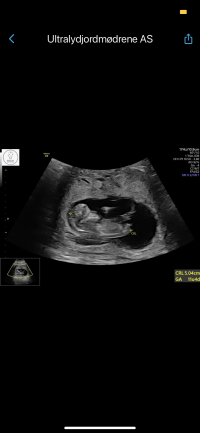

13mm og tilbake igjen til 8+2hematomet kan ses under og mot høyre av fostersekken, og har endret seg veldig, så dette ser lovende ut